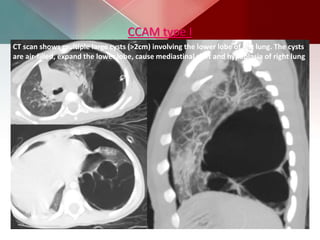

CCAM type I

CT scan shows multiple large cysts (>2cm) involving the lower lobe of left lung. The cysts

are air-filled, expand the lower lobe, cause mediastinal shift and hypoplasia of right lung